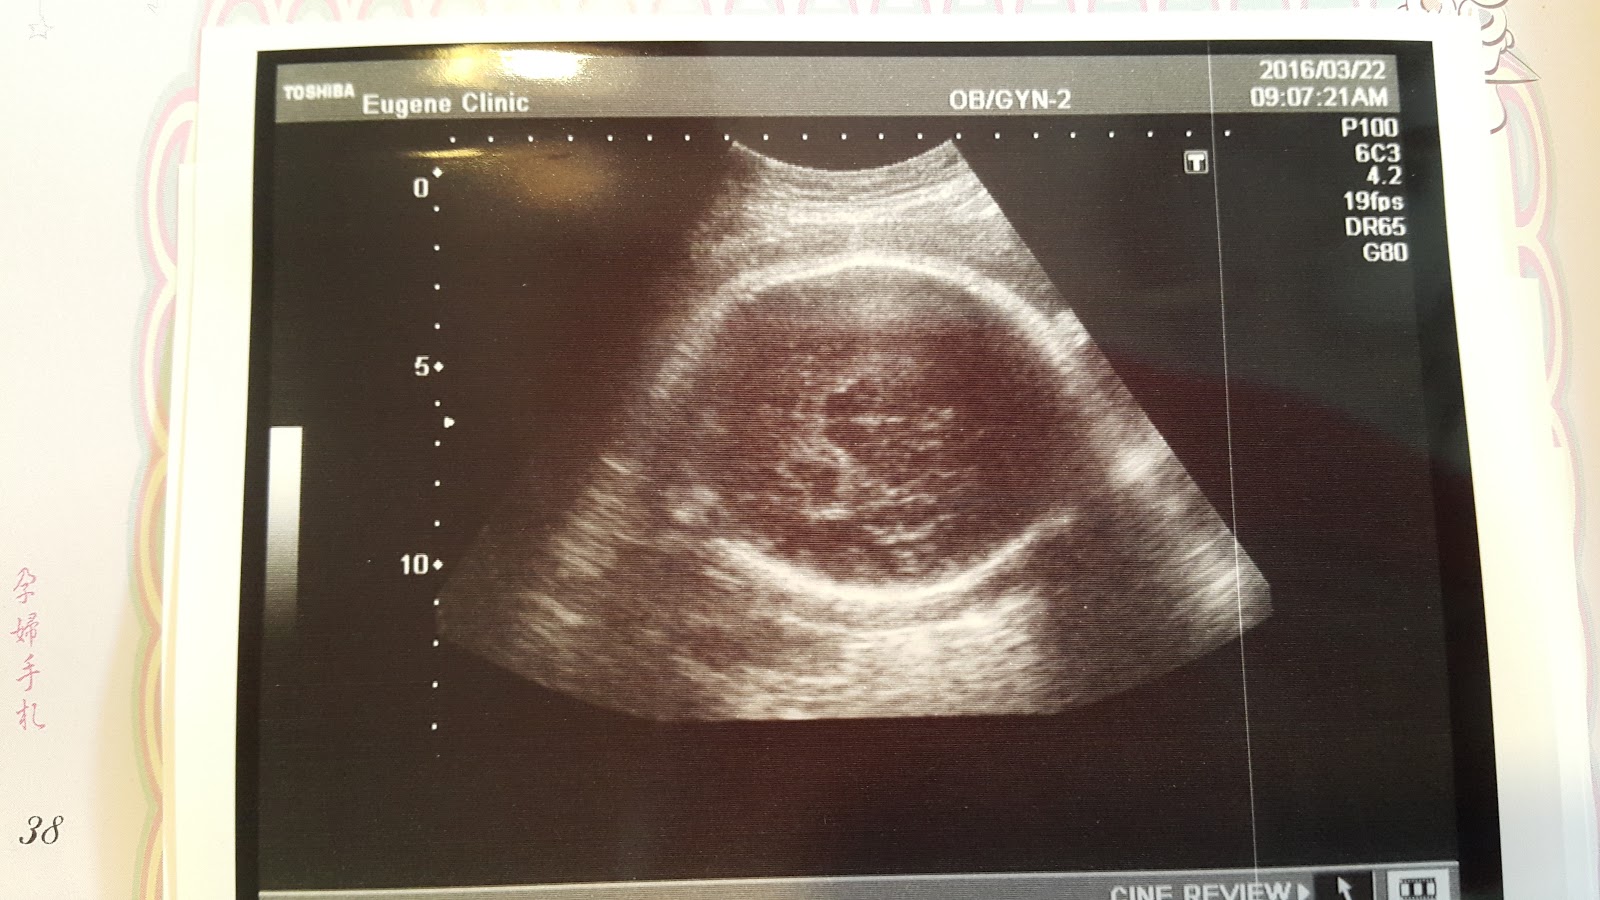

依然頭好壯壯的Haru

超音波一下去就照到腦袋瓜,很可愛~